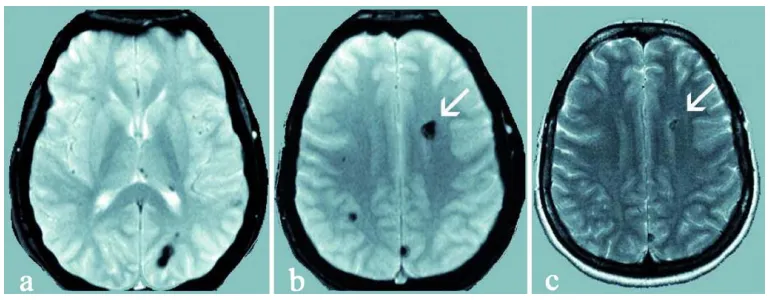

图2 a, b:27岁无症状母亲的多发幕上海绵状血管瘤,呈典型低信号;c 常规T2加权磁共振扫描:显示无症状母亲左额叶最大海绵状血管瘤(白色箭头)。

MRI检查结果显示:无症状母亲脑内实际存在多个海绵状血管畸形小病灶,父亲检查结果完全正常。

对其无症状双亲进行的基因检测和MRI检查显示,27岁母亲携带相同基因突变并存在多发性海绵状血管瘤(图2)。因此,这位初诊为散发病例的患者,现可归类为家族性CCM。